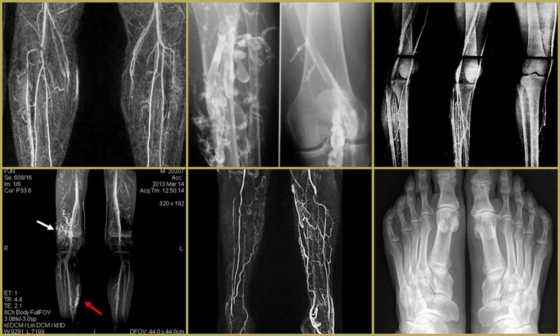

Перед тем, как назначать лечение – необходимо подтвердить наличие заболевания. Для этого нужно записаться на консультацию к специалисту, а также пройти ультразвуковое исследование вен. Дополнительными методами диагностики являются анализы крови и контрастная рентгенография.

Для наглядности посмотрите на фото тромбофлебита нижних конечностей:

- При поражении стопы отмечается отёк на тыльной её поверхности и вздутие подкожных вен, а также синюшный оттенок на кончиках пальцев;

- Тромбофлебит голени характеризуется равномерными отёками, которые лучше просматриваются на передней поверхности. На коже могут появляться сосудистые звёздочки или синие точечные пятна. Для наглядности можно сравнить правую и левую ноги;

- При наличии тромба в сосудах бедра обычно отекает внутренняя её поверхность, при поражении поверхностных вен наблюдается синий сетчатый рисунок по её ходу. Если сгусток находится в просвете глубокого сосуда – отмечается отёчность и цианоз всей конечности.

Зная, как выглядит тромбофлебит на ногах, можно сэкономить время, обратившись к нужному специалисту.